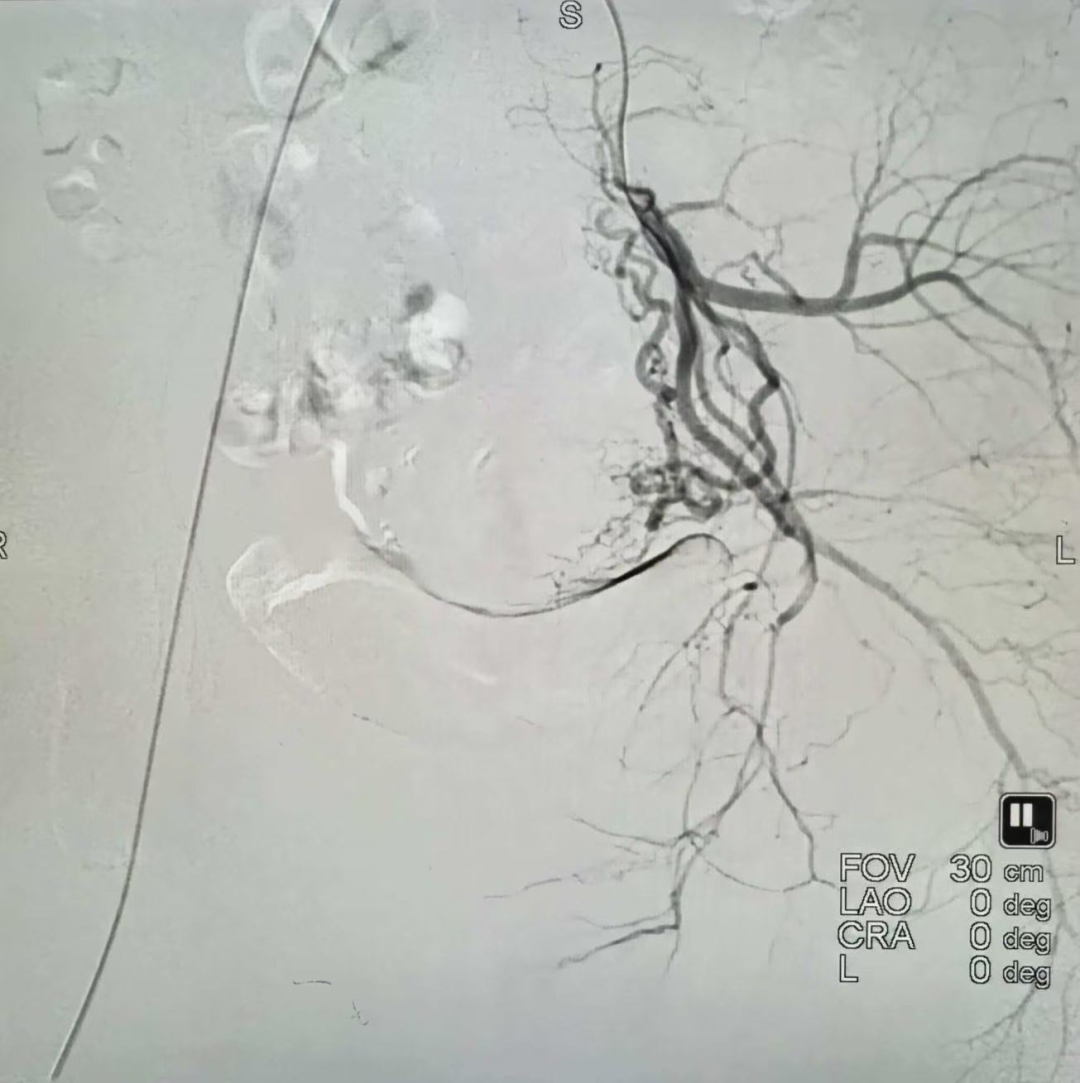

子宫动脉栓塞前

子宫动脉栓塞后

在超声科的精准引导下,妇产科团队顺利为她实施了妊娠物清除术。术后下段出现约 200 ml 活动性出血,医护团队即刻启动预设方案,放置球囊压迫止血,全程操作精准、平稳。